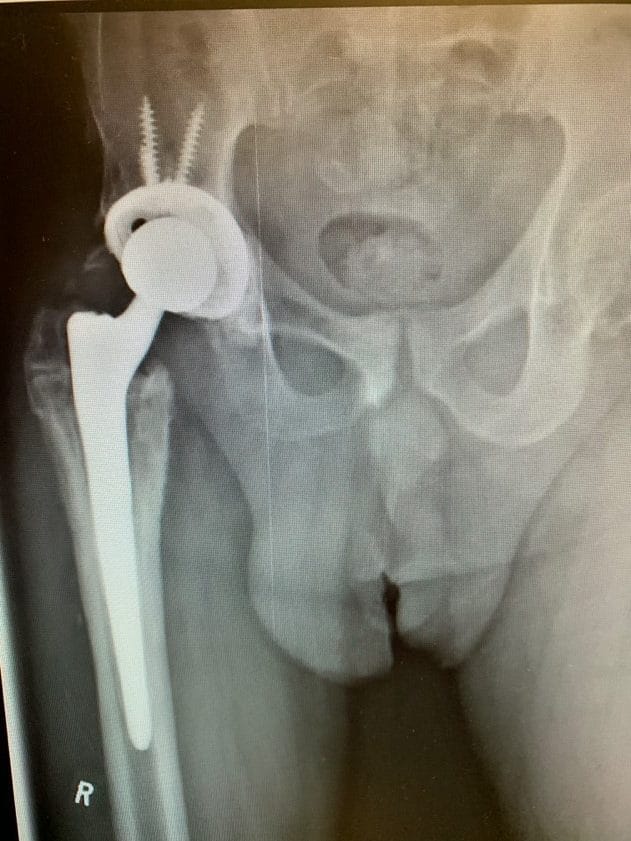

Her X-rays revealed her previous surgical hardware and a healed femur fracture with a small malunion in her femoral canal. Her hip was severely arthritic, with almost no joint space visible at all.

Pre-op